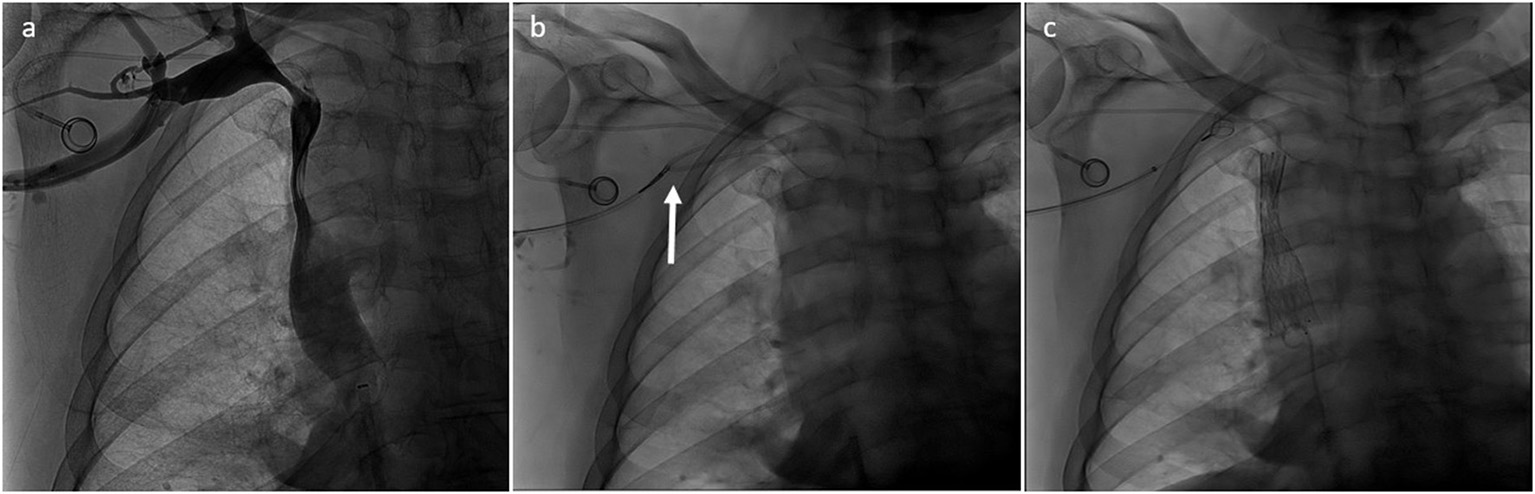

Figure 2

(a,b) Type I SVCO in a patient with a well-positioned implanted central venous catheter. (c) Stenting of the SVC was performed without repositioning of the catheter tip which ends below the stent.